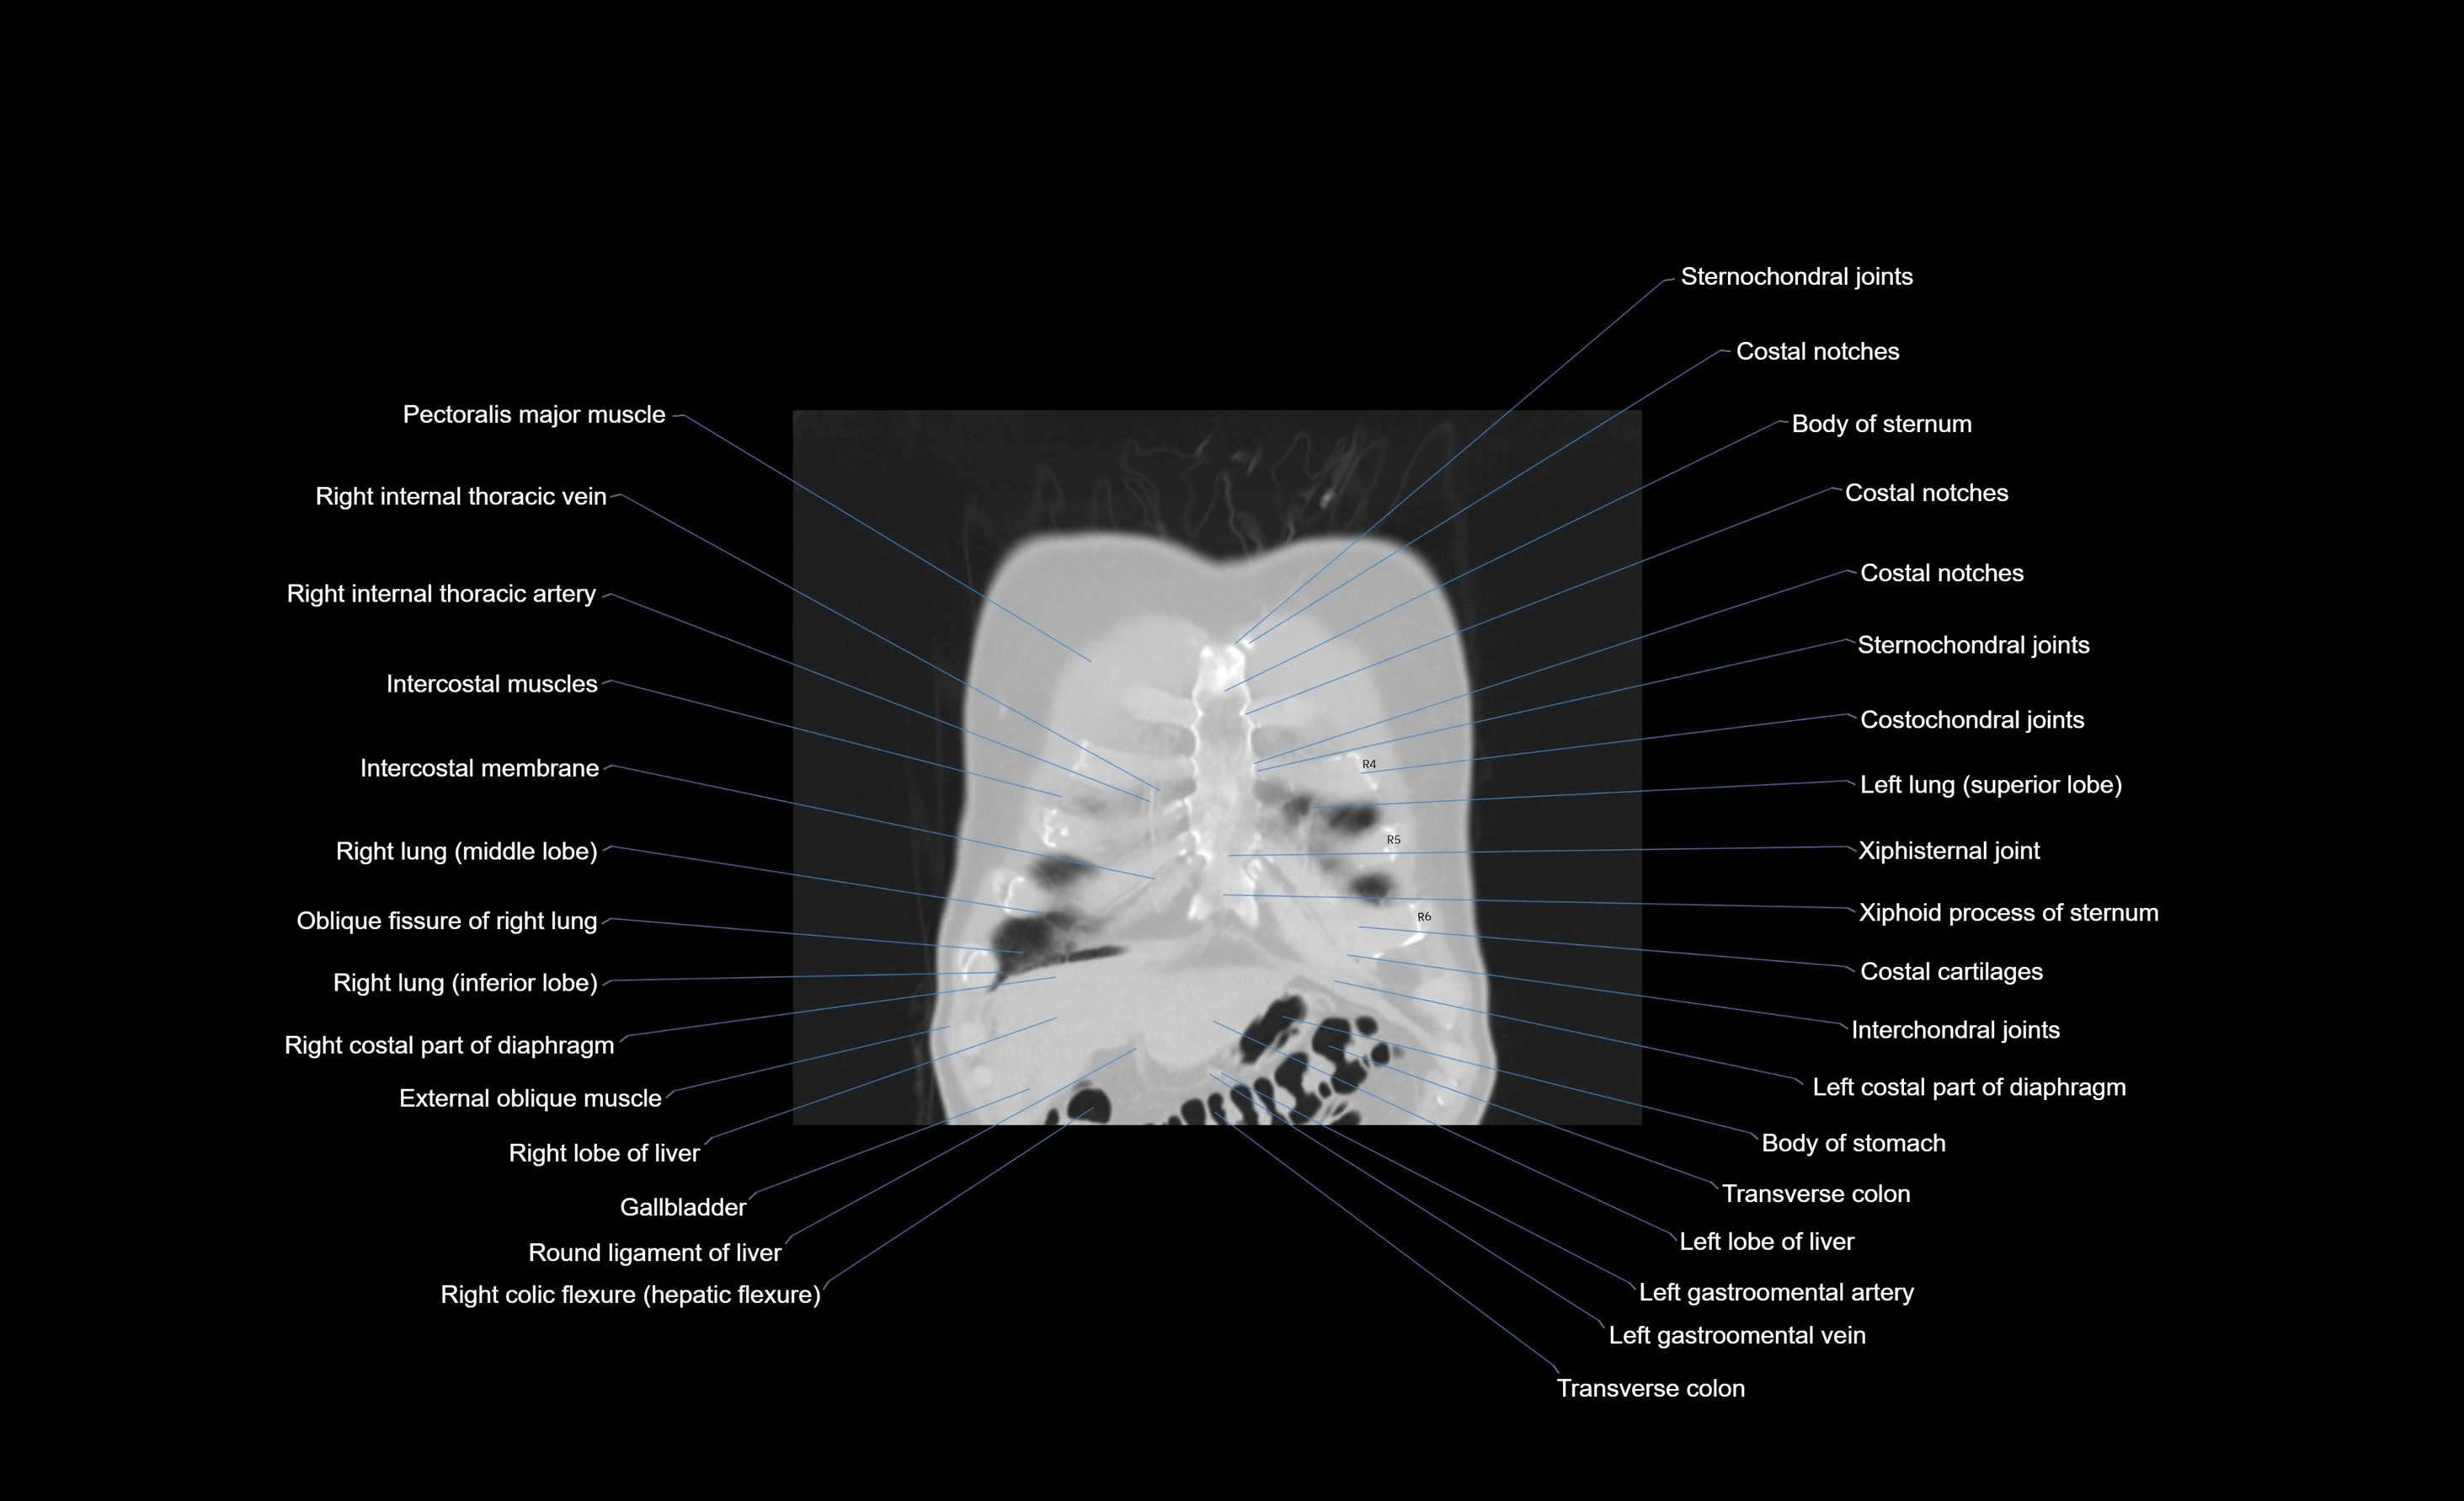

- Pectoralis major muscle

- Internal thoracic artery

- Internal thoracic veins

- Intercostal muscles

- Right lung (middle lobe)

- Oblique fissure of right lung

- Right lung (inferior lobe)

- Costal part of diaphragm

- External oblique muscle

- Right lobe of liver

- Gallbladder

- Ligamentum teres (round ligament of the liver)

- Transverse colon

- Left lobe of liver

- Left hemidiaphragm

- Body of sternum

- Costal notches

- Costochondral joints

- Costal cartilages

- Xiphisternal joint

- Xiphoid process of sternum